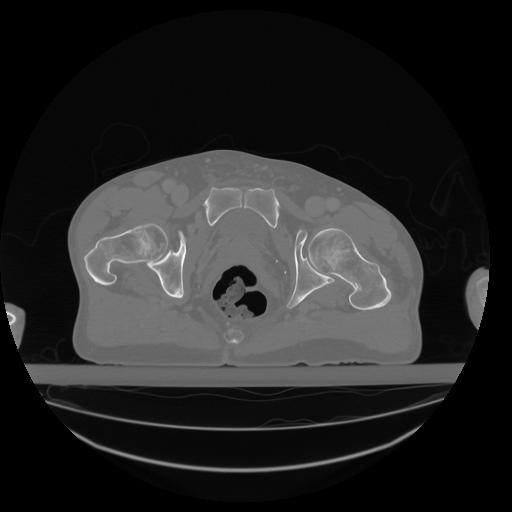

34 CUERPO,CE,Vol,1.0,CUERPO,,